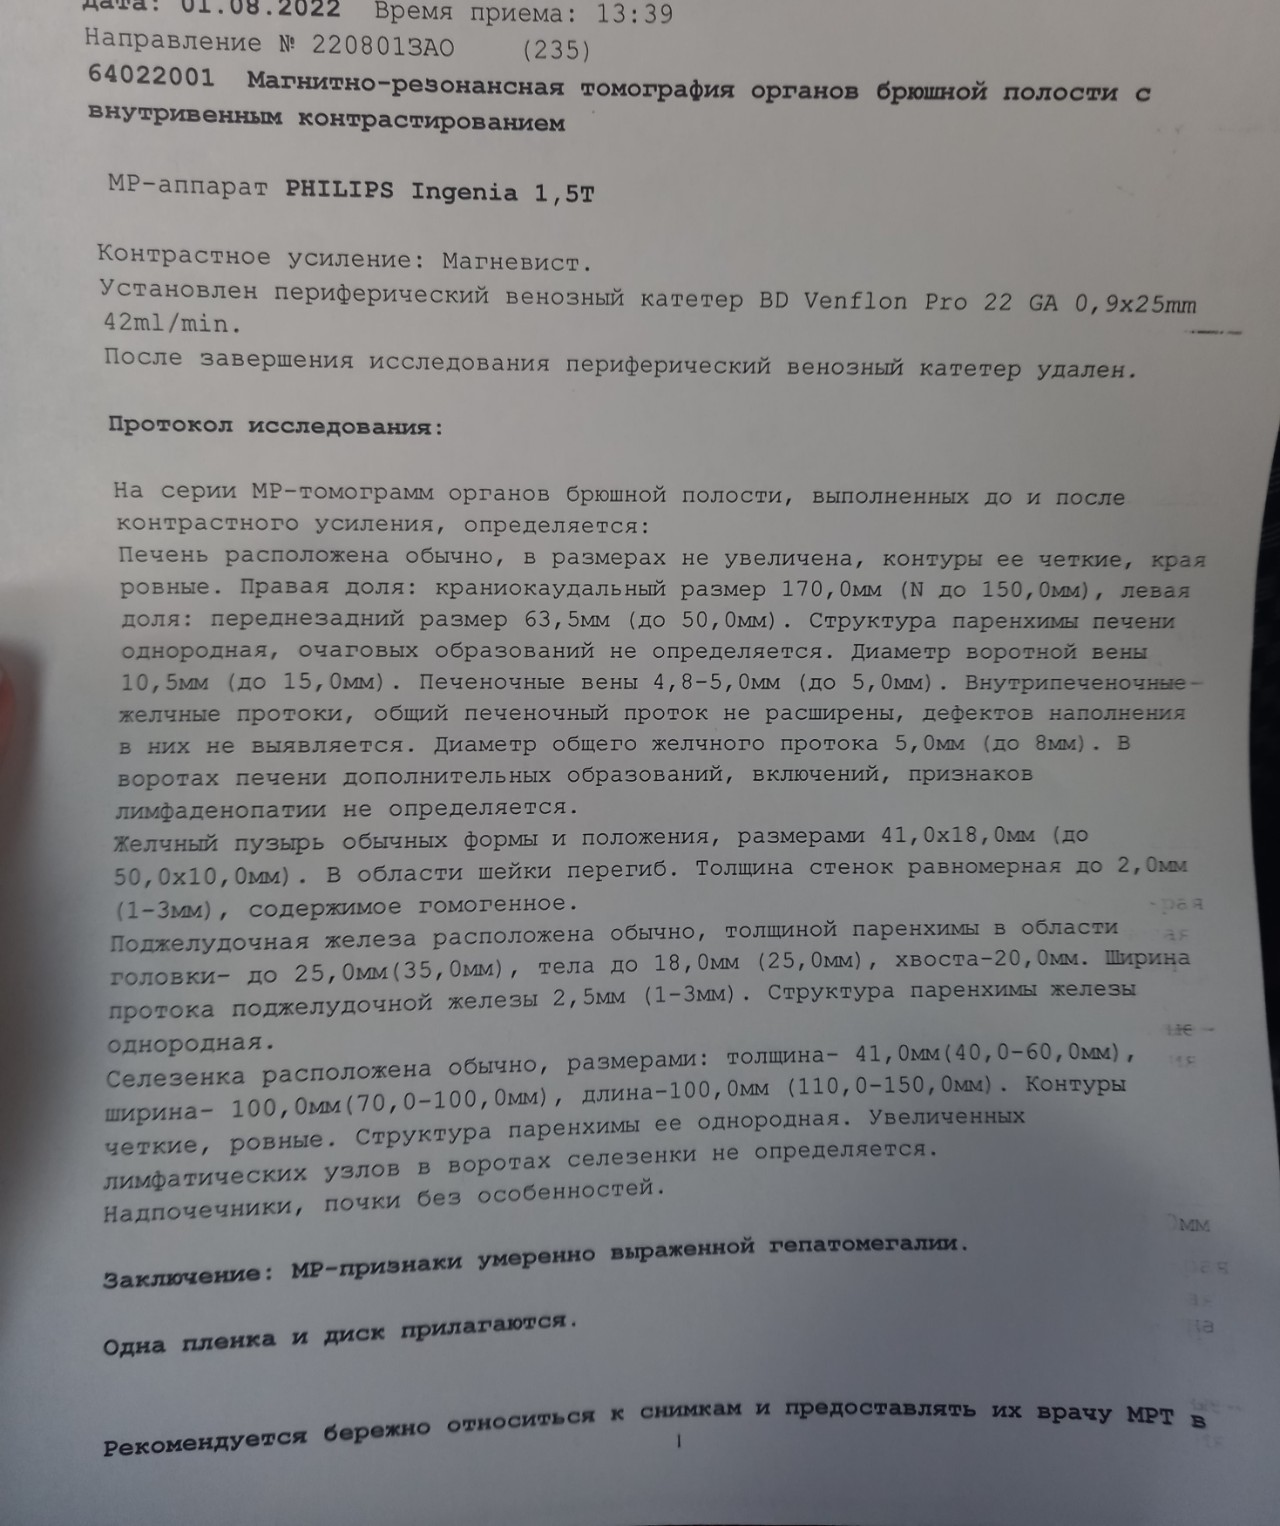

Медицинские термины на фото: визуальное пособие